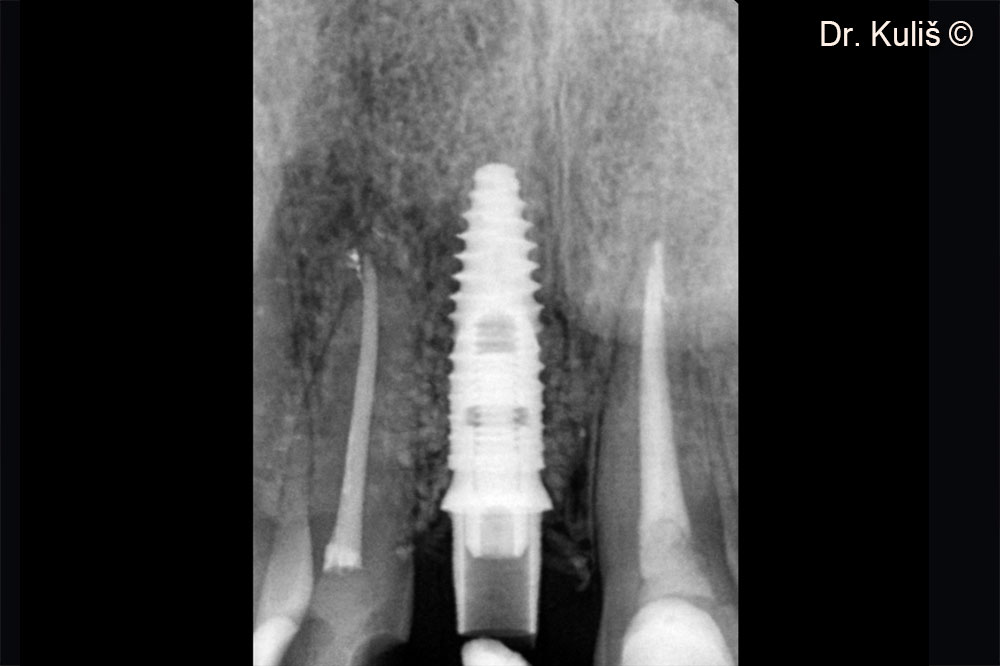

Vị trí cấy ghép có đường kính 3,75mm.

Ảnh chụp X-quang sau giai đoạn thứ hai